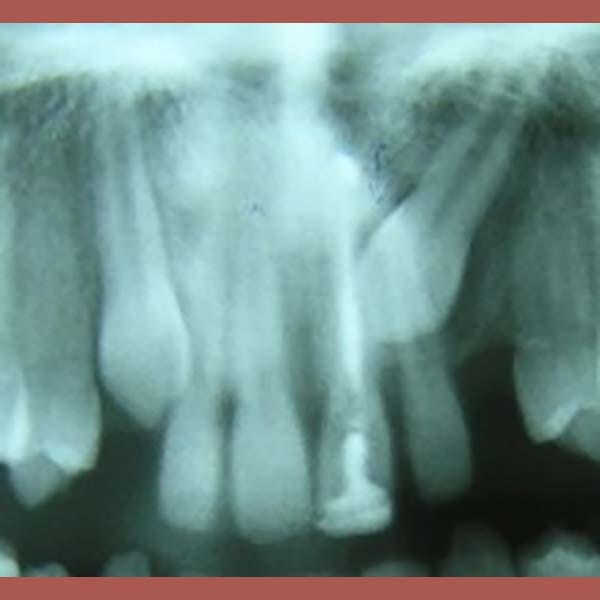

يعتبر انطمار الأنياب العلوية في العظم من الحالات التي تتطلب تدخلاً تقويمياً دقيقاً. بصفتي أخصائي تقويم أسنان في العين، أعمل على خطط علاجية تضمن إنزال هذه الأسنان بأمان. هذه الحالة توضح خطوات علاج الناب المنطمر بالتقويم، من فتح المسافة إلى جره لمكانه الصحيح.

كانت المشكلة الرئيسية في هذه الحالة هي وجود ناب علوي منطمر بالكامل في عظم الفك، وغير قادر على البزوغ بشكل طبيعي.

بعد التشخيص الدقيق، وضع الدكتور خالد الكاتب خطة علاجية من مرحلتين باستخدام تقويم الأسنان: